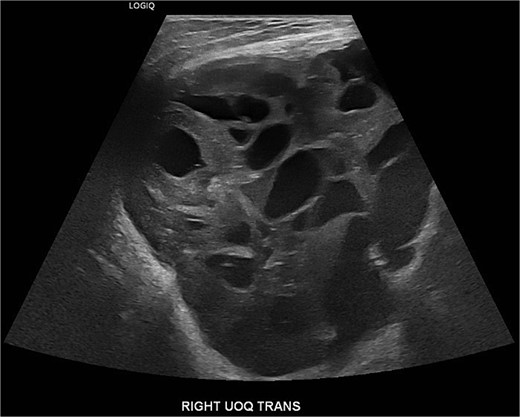

A 19-year-old Hispanic female with no significant past medical history presented to the emergency department with a rapidly growing right breast mass. She reported first noticing the mass at age fourteen, at which point it was small and stable in size until approximately two months prior, when it began to grow and become painful, ultimately causing complete distortion of the breast and nipple areolar complex (Fig. 1). An ultrasound at that time revealed a large complex mass measuring 19 × 17 × 23 cm, with multiple solid and cystic components and no increased vascularity (Fig. 2). The mass was classified as BI-RADS 4.

An ultrasound at that time revealed a large complex mass measuring 19 × 17 × 23 cm, with multiple solid and cystic components and no increased vascularity, consistent with BI-RADS 4.